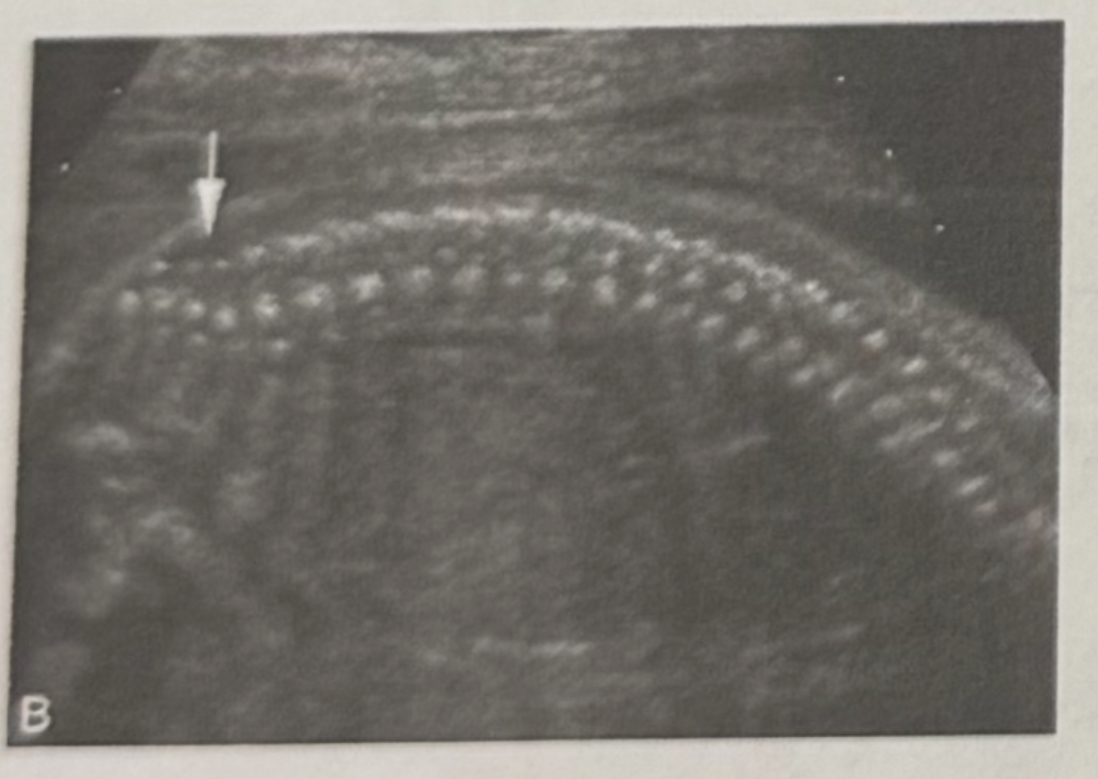

What is the section and what is shown?

a. Sagittal spine

b. Transverse spine

c. Coronal spine

Transverse spine